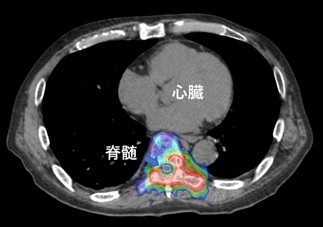

転移性骨腫瘍

腎がん胸椎転移。他に病変がないためIMRTを用いて真ん中の脊髄を外して胸椎に高線量を照射。